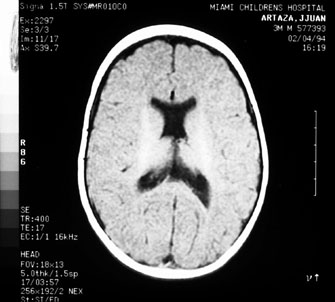

Optic nerve hypoplasia, unless subtle, usually is diagnosed on fundus examination. Although most cases are idiopathic, maternal gestational diabetes and use of phenytoin are well-known risk factors; more recent epidemiologic studies have also suggested that young maternal age, first parity, smoking, and use of fertility and antidepressant drugs may also play a role.27 If bilateral, this condition may be associated with congenital nystagmus. De Morsier's syndrome (septo-optic dysplasia) refers to the constellation of bilateral optic nerve hypoplasia, absence of the septum pellucidum (Fig. 5), thinning or absence of the corpus callosum, dysplasia of the anterior third ventricle, and pituitary dysfunction (see Chapter 5, Fig. 9). Brodsky and Glasier28 broadened the spectrum of this condition. In a study of 40 children, some optic nerve anomalies were isolated, but in other children, midline craniofacial defects, hemispheric gray matter dystrophic anomalies, and posterior pituitary ectopia were noted. Of 21 cases of optic nerve hypoplasia described by Zeki et al,29 there were midline central nervous system defects in six and endocrine deficiencies in nine. In the series of 35 patients with bilateral optic nerve hypoplasia described by Siatkowski et alet al30 neuroradiographic abnormalities were seen in 46% and endocrinopathies in 27%. Growth hormone deficiency was the most common endocrine abnormality. The visual spectrum ranged from 20/20 in one case to no light perception in 34% of patients; 80% were legally blind (20/200 or less in both eyes). Absence of the septum pellucidum and corpus callosum, with panhypopituitarism, occurred in only 11.5% of all patients with bilateral optic nerve hypoplasia. Recently, a sporadic mutation in the HESX1 gene has been reported to cause optic nerve hypoplasia with pituitary insufficiency.31

Fig. 5. Magnetic resonance image of patient with bilateral optic nerve hypoplasia demonstrating absence of septum pellucidum with single midline ventricle.